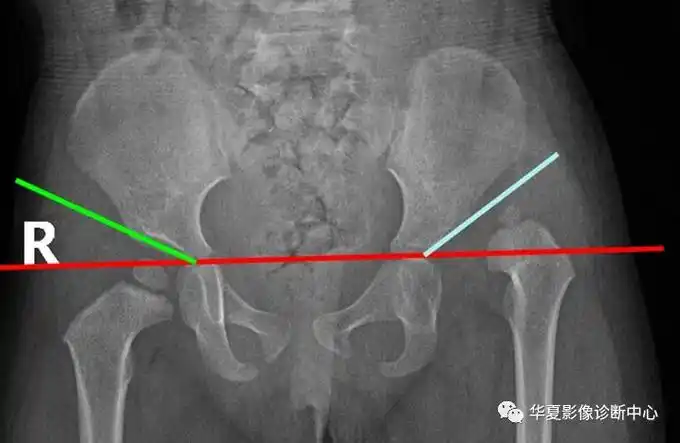

30°,1岁以后不应超过25°,2岁20°,成人10°,如角度增大表示髋臼变浅